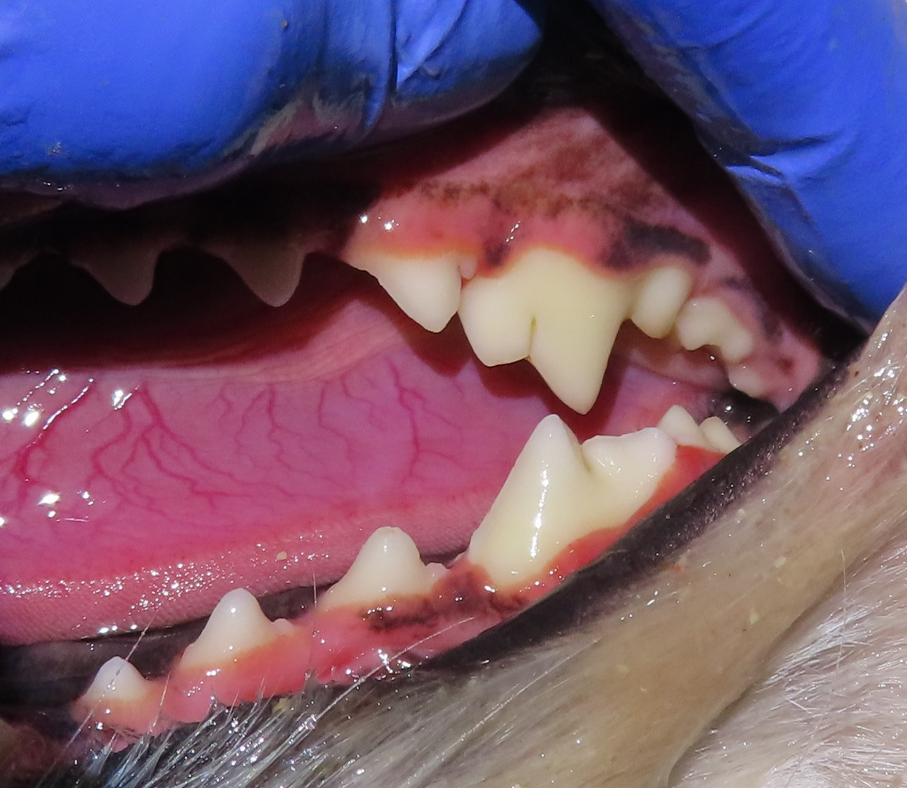

양치를 하다 보니 송곳니 뒤쪽 어금니의 잇몸 라인이 예전보다 내려가 보였고, 치아 표면도 살짝 깨져 있는 것 같아 걱정이 되었다고 하셨습니다.

치석이 쌓이면 잇몸 가장자리부터 염증이 시작됩니다. 초기에는 붉게 보이는 정도지만, 관리 시기를 놓치면 잇몸 높이가 점차 내려가는 치은퇴축으로 이어질 수 있습니다. 보호자 입장에서는 잇몸이 내려가 보이면 상태가 이미 심각해졌다고 느끼기 쉽습니다.

이번 사례의 아이 역시 송곳니 뒤쪽 어금니 부위에 치은퇴축이 관찰되었고, 치아 표면 일부에 미세한 파절이 확인되었습니다. 겉으로 보기에는 발치를 고려해야 할 것처럼 보일 수 있는 상태였습니다.